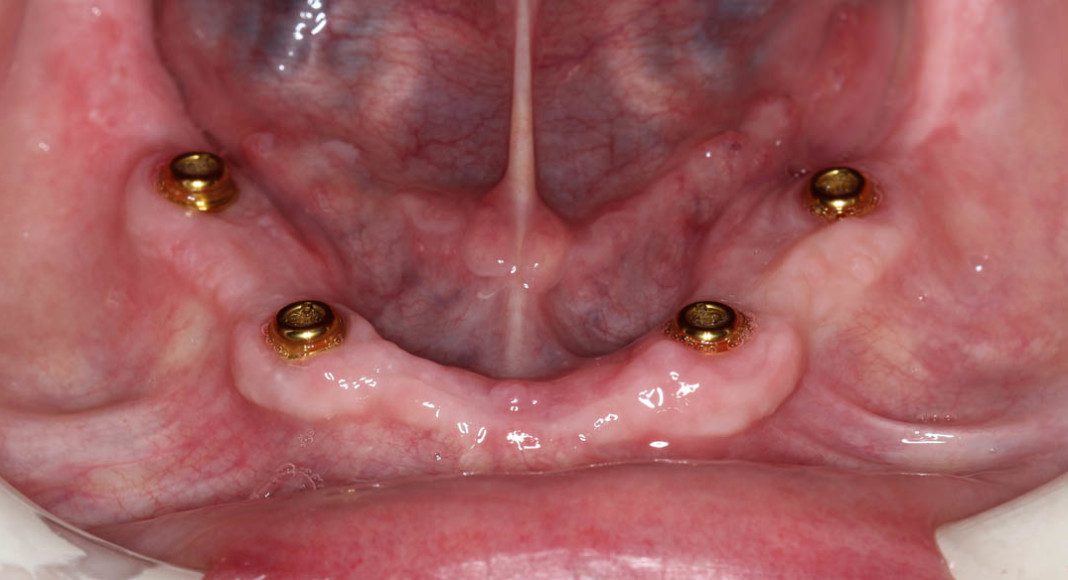

Upper jaw with healing caps over implants. Two months after implants are placed, the process of fabricating the overdentures begin. This process is nearly identical to making complete dentures (without implants). When I lecture, I tell the audience of dentists that, “implants only partially rescue poorly made dentures”! Meaning, for an optimum outcome, it requires great dentures connected to well placed implants.